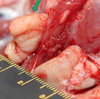

4 y.o. cat S/F, progressive weight loss

What are the possible DDxs for this lesion? What is the actual diagnosis?

DDxs: gingivitis due to FIV, SCC, renal failure, calicivirus

Actual diagnosis: SCC